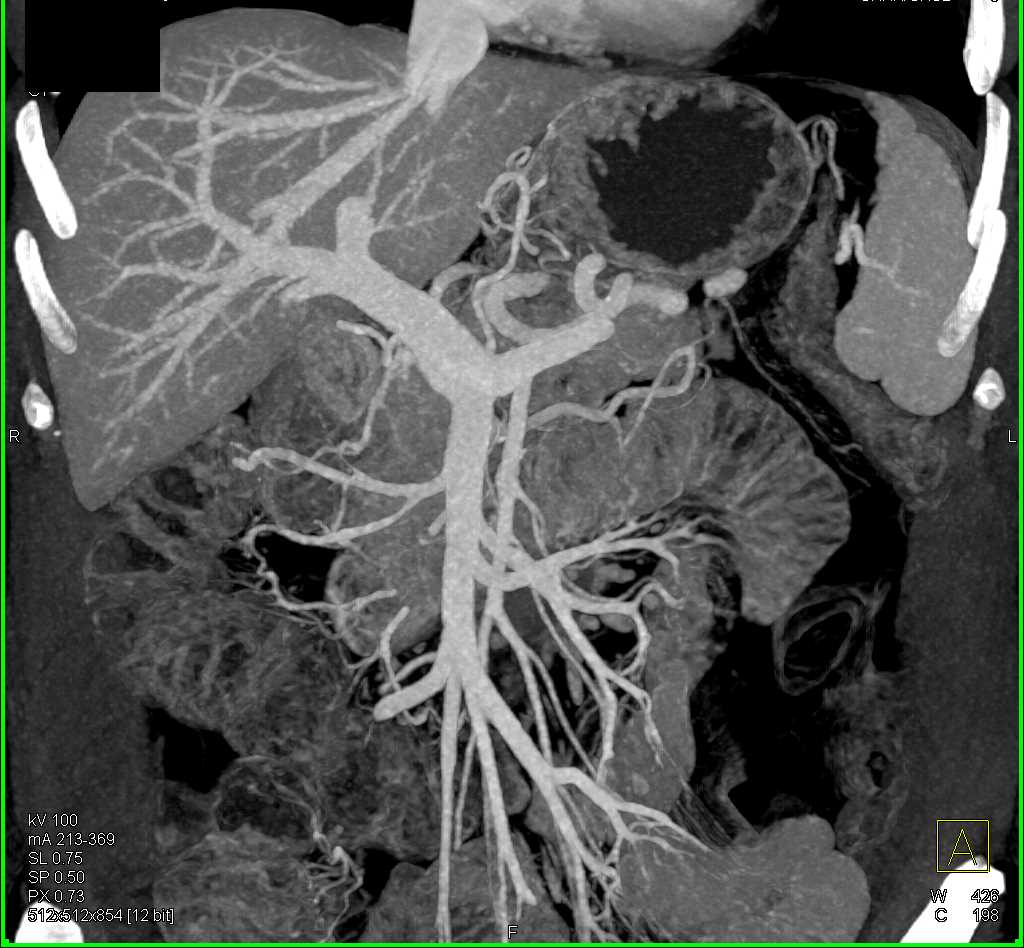

Duodenal Carcinoma with Obstruction